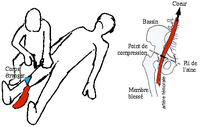

الطرف السفلي